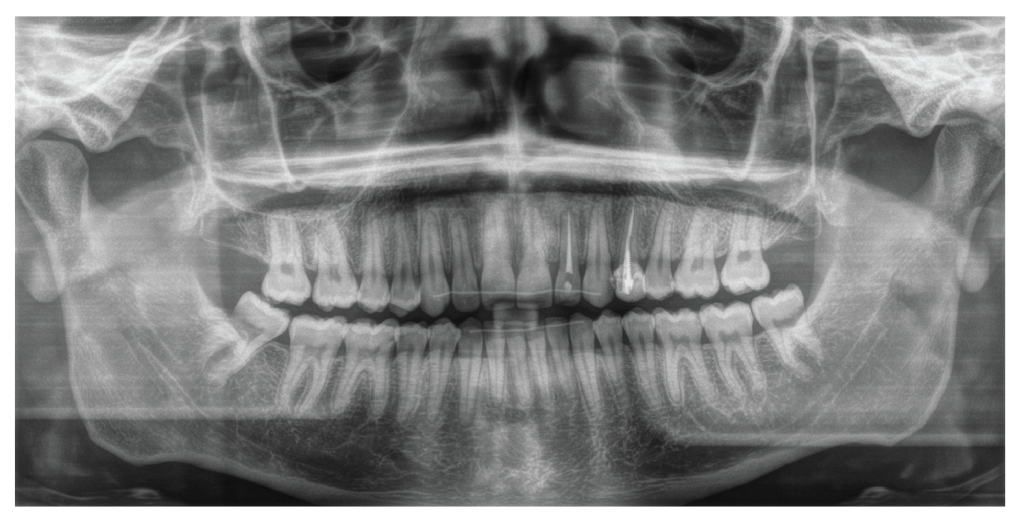

The panoramic radiograph (Figure 3) revealed a complete dentition except for the maxillary third molars, which had been previously extracted. The roots of all teeth were fully developed, but there were signs of blunting on the maxillary left central and a fracture at the tip of the apex on the maxillary lateral incisor. Remodeling of the condyles was also observed. Lateral cephalometric analysis (Figure 4 and Table I) revealed a skeletal Class I relation (ANB= 2°) with a hypo-divergent mandible (FMA = 19.5°). The inclinations of the maxillary and mandibular incisors were within normal limits, with U1°- SN measuring 101.2° and IMPA measuring 99.3°, respectively). Soft tissue analysis indicated that the distances from the upper and lower lips to the E-line were deficient, measuring -4.9 mm and -5.2 mm, respectively.

Figure 3: Pre-treatment panoramic radiograph. Panoramic radiograph shows a complete dentition except for the absence maxillary third molars, with the roots of all teeth fully developed. Signs of blunting on the maxillary left central, and a fracture at the tip of the apex on the maxillary left lateral incisor can be observed. Remodeling of the condyles is also visible. Mandibular morphology shows prominent gonial angles.